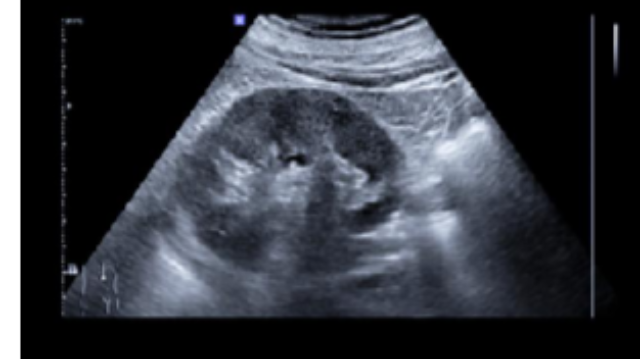

結(jié)石臨床解決方案在技術(shù)協(xié)同方面,現(xiàn)代肝膽結(jié)石診療充分融合了內(nèi)鏡、腹腔鏡、超聲介入等多種微創(chuàng)手段。例如ERCP(經(jīng)內(nèi)鏡逆行胰膽管造影術(shù))可經(jīng)口腔自然腔道直達(dá)膽管取石,避免開(kāi)腹創(chuàng)傷;而腹腔鏡聯(lián)合膽道鏡技術(shù)則能在切除膽囊的同時(shí),通過(guò)膽囊管超微創(chuàng)通道移除膽總管結(jié)石,實(shí)現(xiàn)“單次手術(shù)解決多部位結(jié)石”的目標(biāo)。對(duì)于肝內(nèi)局限型結(jié)石合并肝組織萎縮的患者,腹腔鏡肝部分切除術(shù)可同步移除病灶并修復(fù)受損組織結(jié)構(gòu),從根源降復(fù)發(fā)風(fēng)險(xiǎn)。這種技術(shù)組合打破了傳統(tǒng)單一療法的局限,使不同部位、不同復(fù)雜程度的結(jié)石均能獲得針對(duì)性解決。

針對(duì)肝膽結(jié)石的臨床解決方案,當(dāng)前醫(yī)學(xué)實(shí)踐提供了多層次的干預(yù)路徑,兼顧個(gè)體差異與解決**性。在無(wú)癥狀或結(jié)石體積較?。ㄈ缰睆叫∮?.5厘米)的情況下,可通過(guò)調(diào)整生活方式干預(yù),例如增加飲水量、規(guī)律運(yùn)動(dòng)及脂飲食,維持膽汁代謝平衡。對(duì)于膽固醇型結(jié)石,口服溶石藥物如熊去氧膽酸可促進(jìn)結(jié)石溶解,尤其適用于直徑0.5-1.5厘米的病例,但需長(zhǎng)期用藥并配合定期監(jiān)測(cè)。微創(chuàng)技術(shù)是現(xiàn)代肝膽結(jié)石管理的方向。內(nèi)鏡逆行胰膽管造影(ERCP)通過(guò)自然腔道進(jìn)入膽管,直接移除結(jié)石或放置支架引流,適用于膽管炎等并發(fā)癥患者,其可視化操作能降創(chuàng)傷風(fēng)險(xiǎn)。復(fù)發(fā)預(yù)防機(jī)制完善,長(zhǎng)期有效。

可根據(jù)結(jié)石特性提供多元化選擇,緩解患者不適感受。對(duì)于直徑較小的結(jié)石,藥物方案通過(guò)調(diào)節(jié)尿液成分來(lái)促進(jìn)自然排出,同時(shí)成分可減輕排尿過(guò)程中的不適感。針對(duì)5-15mm的中型結(jié)石,體外聲波震蕩技術(shù)成為常用手段,該過(guò)程無(wú)需切口,恢復(fù)周期相對(duì)較短。當(dāng)面對(duì)鈣質(zhì)包裹的致密型結(jié)石時(shí),分階段解決方案可提升整體效果。對(duì)于體積超過(guò)20mm的復(fù)雜結(jié)石,輸尿管鏡或經(jīng)皮腎鏡方案能直接解決目標(biāo)位置,降周邊組織影響。完成干預(yù)后,持續(xù)的飲水建議及飲食調(diào)整建議可維持尿液通暢,減少?gòu)?fù)發(fā)可能。部分**單位還提供全天候解決服務(wù),及時(shí)緩解突發(fā)性疼痛。中醫(yī)方案注重整體調(diào)理,采用芍藥等成分舒緩痙攣,川楝子等藥材輔助尿路擴(kuò)張,形成協(xié)同作用。隨訪復(fù)查機(jī)制則動(dòng)態(tài)跟蹤恢復(fù)進(jìn)程。這些方案共同構(gòu)建了兼顧即時(shí)需求與長(zhǎng)期管理的完整體系。**指導(dǎo)詳細(xì),預(yù)防再次形成效果明確。安徽本地結(jié)石臨床解決方案成本價(jià)